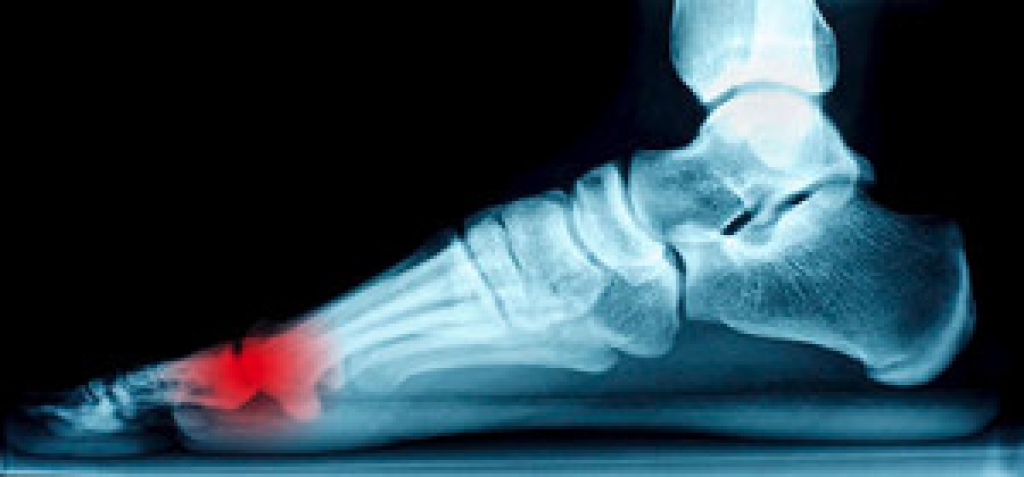

The medical condition that is known as sesamoiditis can cause pain in the joints of the big toe. It can happen as a result of inflammation of the sesamoid bones, which are two bones that are found beneath that joint. These particular bones are found inside tendons that are attached to the bones, and if an injury occurs, the entire area may become painful, which may cause difficulty in walking. The sesamoid bones may be impacted if an injury occurs, or if there is an abnormal foot structure present. Relief may be found when the injured foot is elevated, as this may diminish a portion of existing pain and swelling. If you feel you have pain in this part of your foot, and are exhibiting symptoms of sesamoiditis, it is suggested that you speak with a podiatrist who can properly diagnose and treat this condition.

Sesamoiditis is a condition of the foot that affects the ball of the foot. It is more common in younger people than it is in older people. It can also occur with people who have begun a new exercise program, since their bodies are adjusting to the new physical regimen. Pain may also be caused by the inflammation of tendons surrounding the bones. It is important to seek treatment in its early stages because if you ignore the pain, this condition can lead to more serious problems such as severe irritation and bone fractures.

Treatment for sesamoiditis is non-invasive and simple. Doctors may recommend a strict rest period where the patient forgoes most physical activity. This will help give the patient time to heal their feet through limited activity. For serious cases, it is best to speak with your doctor to determine a treatment option that will help your specific needs.